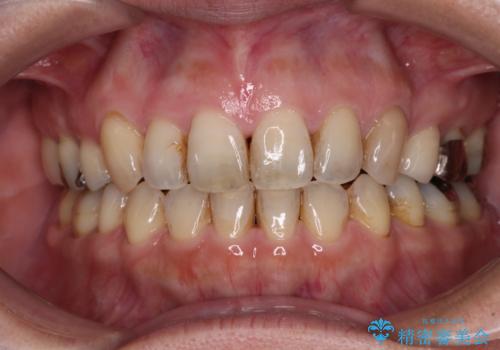

- コンポジットレジンやクラウンなど、様々な医院で治療を受けたために、統一感がなくなってしまった前歯を綺麗にしたいとのことで来院された患者様です。

黄ばんだ前歯や白すぎたクラウン、プラスチックの継ぎ接ぎなどを全てオールセラミッククラウンの統一感のある前歯に仕上げました。